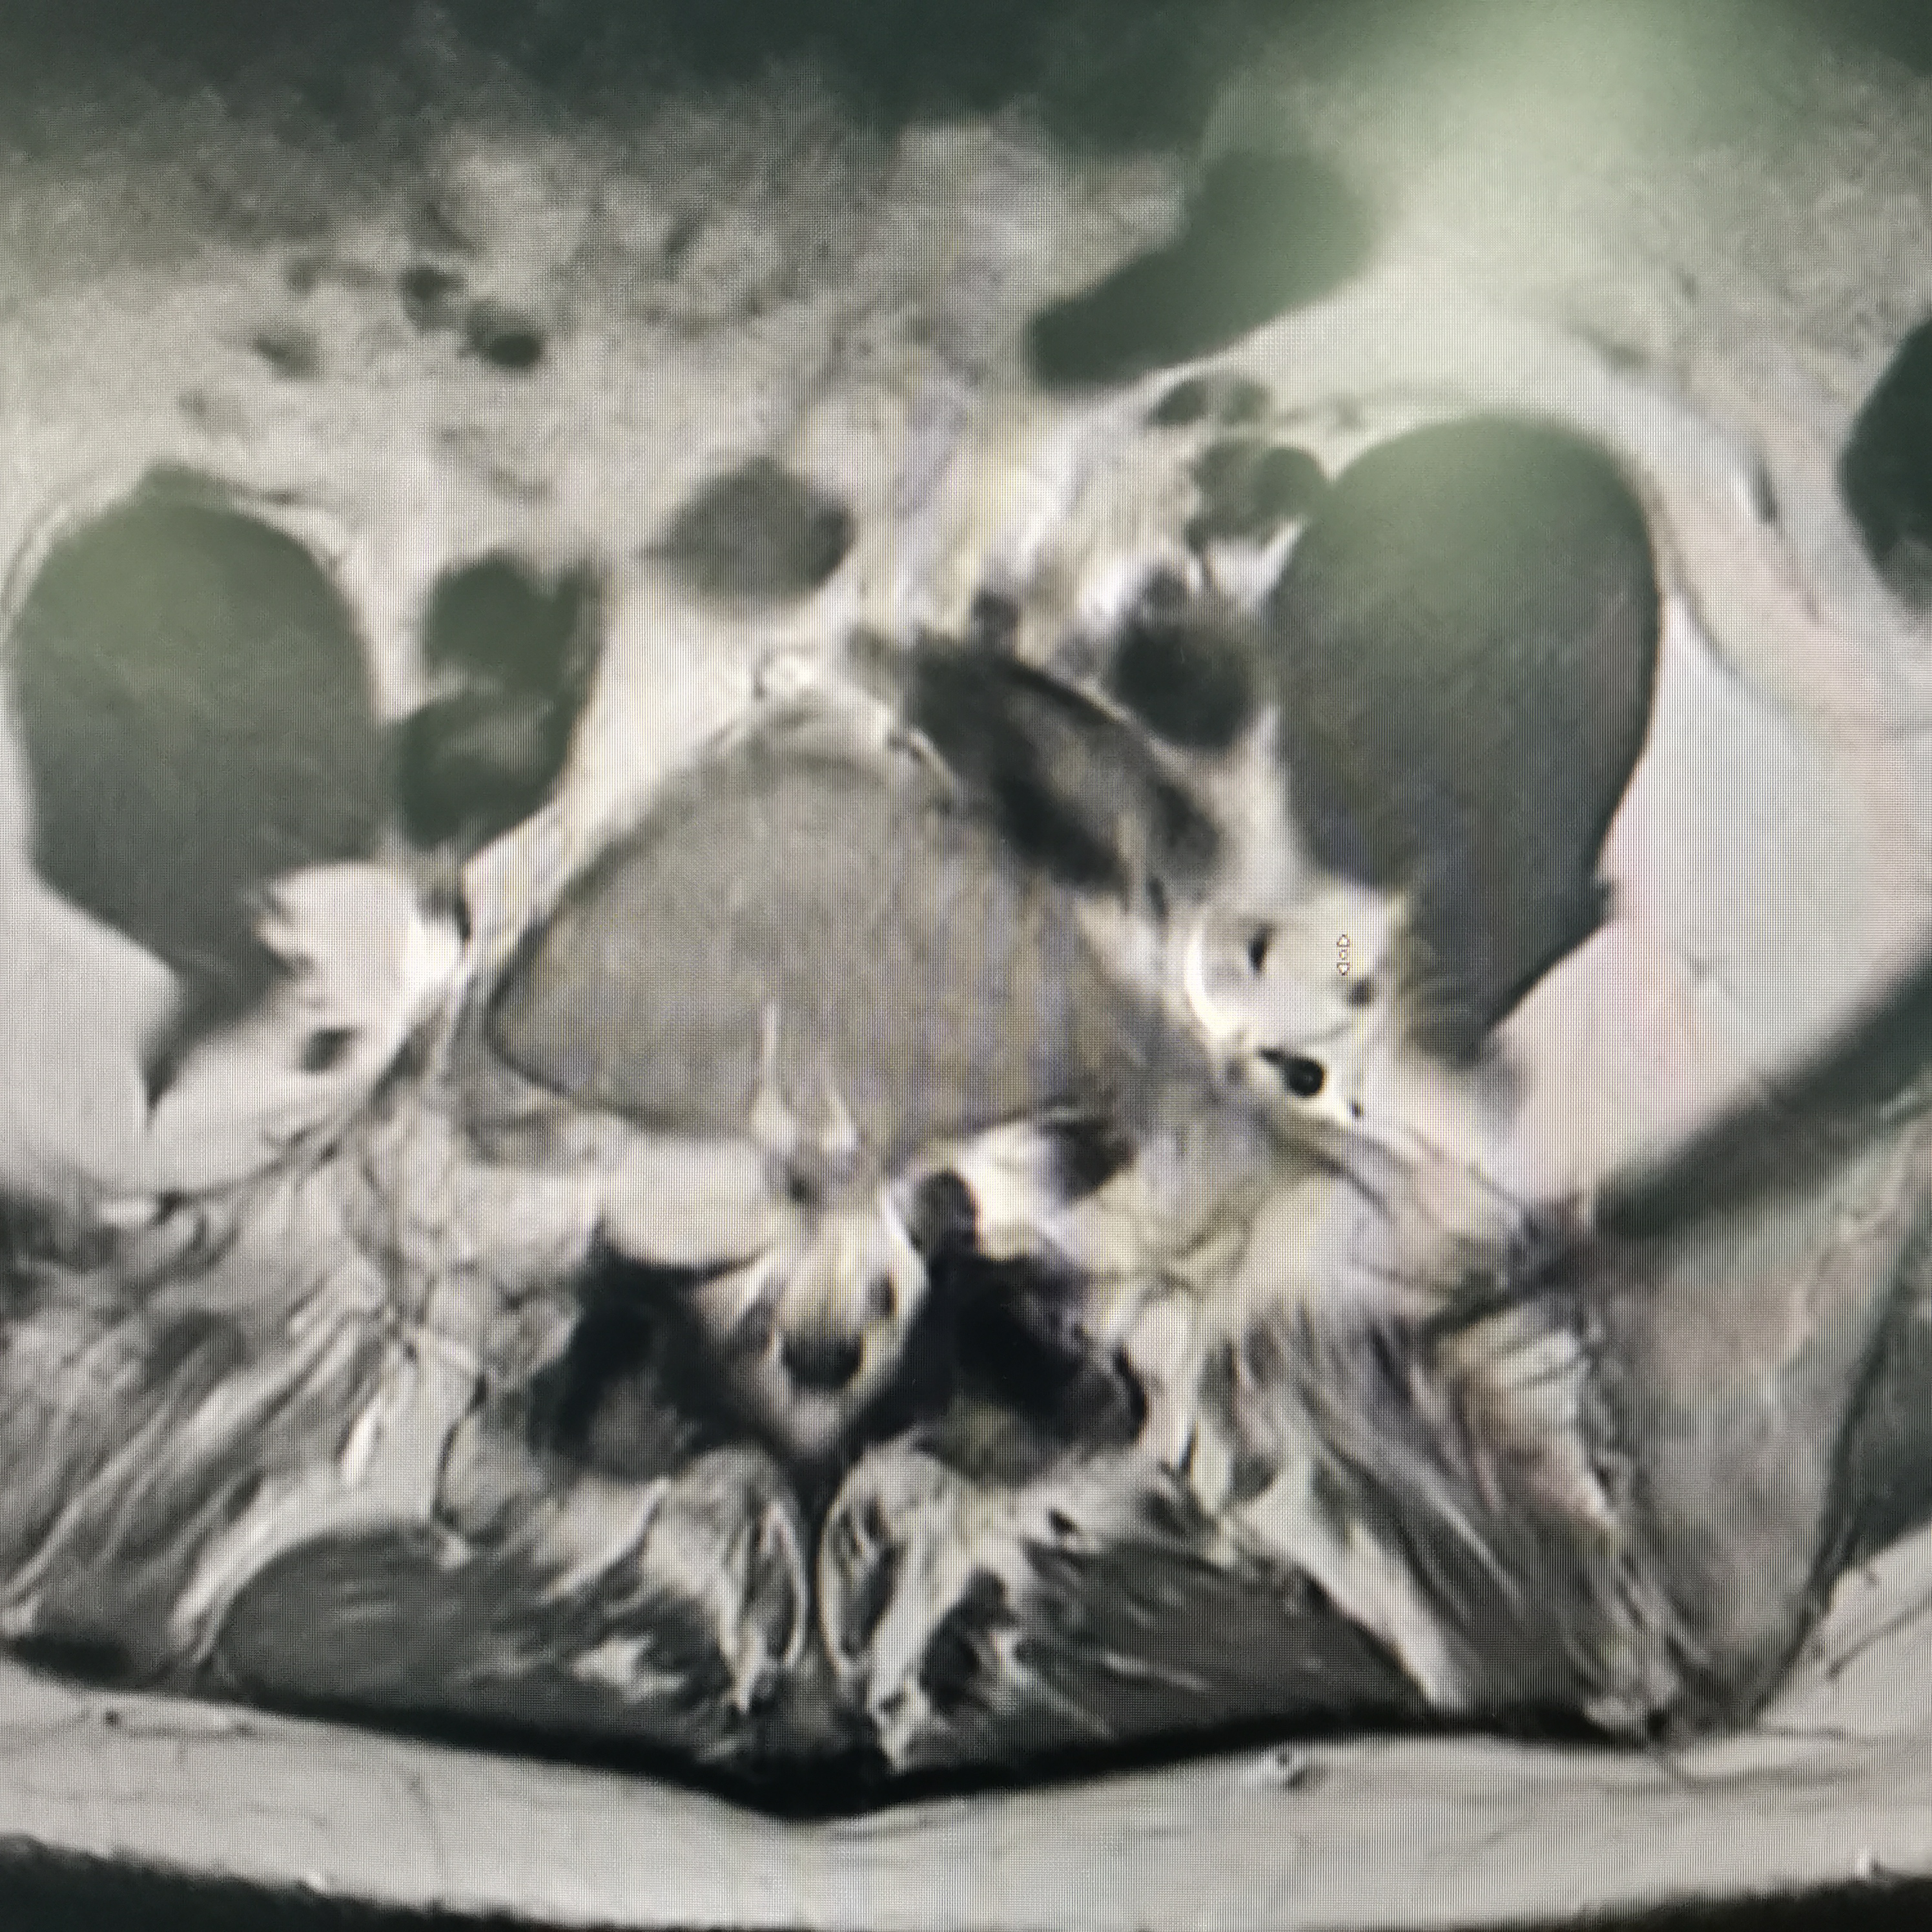

膝关节疼痛,原因是椎管内肿瘤,哑铃型生长,全切肿瘤,保留神经,疼痛症状消失…